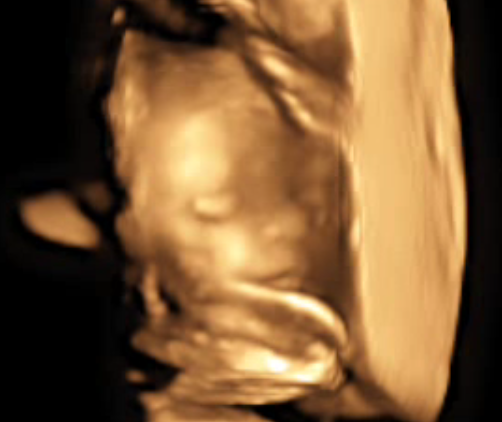

По последним 3d узи, которые я делала в Москве, все хорошо с малышкой. Только сидела пока на попе. или вообще поперек, вытянув ножки, как на шезлонге) потом фото приложу. Ножки мои по фото, все говорят. А вот носик пока кажется картошечкой) но может просто личико маленькое. Главное - что здорова вроде! надеюсь, за 2 недели перевернется.

P.S. Прикреплю и дочины фото на память. Буду вспоминать, как она там ножку на ногу лежала с вытянутыми ножками, как за пуповину держалась ручкой, как -будто в трамвае за перекладину)